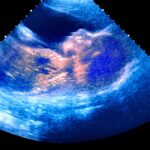

The slew of pro-life legislation (SB 918, HB 1102, HB 1904, HB 2441, SB 778, SB 779, SB 960, SB 647, SB 584) would ban abortion after a baby’s heartbeat is detected, restrict abortion drugs, require abortionists to be board certified in obstetrics and gynecology, and label abortion as “unprofessional conduct.”

The bills also would restore Oklahoma’s abortion ban if Roe v. Wade is overturned, ban fetal trafficking, protect relinquished babies, and require birthing centers and other medical facilities to have policies honoring the remains of babies born through miscarriages or born stillborn.

Stitt’s actions follow media uproar and pro-life praise over Texas’ Heartbeat Act, which bans abortion after a baby’s heartbeat can be detected at about six weeks. The Supreme Court ruled 5-4 to deny abortion providers’ requests to block Texas’ new law last week.